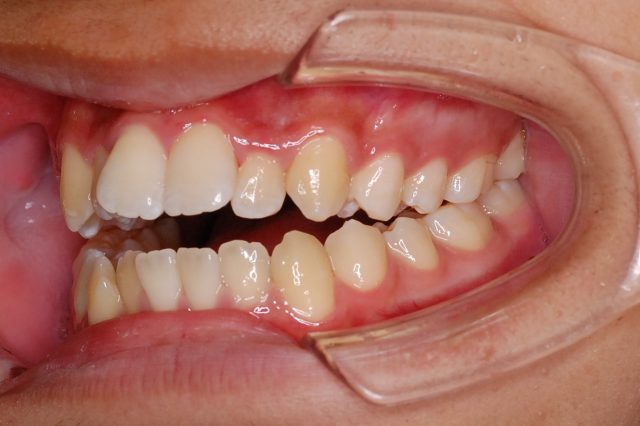

Before

After

主訴

前歯で噛めない

治療期間・回数

2年6ヶ月・30回

治療方法

マルチブラケットにて上下左右4本抜歯

費用

850000+税

デメリット・注意点

歯根吸収 歯肉退縮